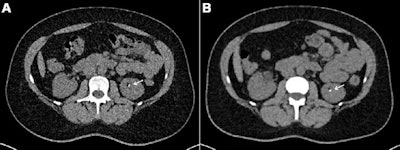

Photon-counting CT (PCCT) directly captures x-ray photons as electric signals without having to then convert them to light, as conventional CT has to do. This capability translates to better spatial resolution, higher iodine image contrast, and better radiation dose efficiency, studies suggest.

Axial contrast-unenhanced abdominal CT examinations in a 38-year-old female patient with a body mass index (calculated as weight in kilograms divided by height in meters squared) of 31.23 with known renal calculi for recurring events of flank pain. The patient underwent (A) dose-optimized energy-integrating detector CT (1.49 mSv) and (B) submillisievert photon-counting detector CT (0.94 mSv). Images from both examinations showed a 3-mm calculus in the left kidney (arrows). Image and caption courtesy of the RSNA.